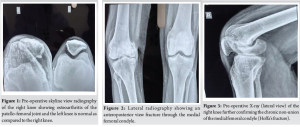

Radiographic evaluation revealed a non-union of the medial femoral condyle consistent with a chronic Hoffa’s fracture (Fig. 1-3). Joint space narrowing and irregularity of the articular surface were also observed, indicating degenerative changes. After multidisciplinary consultation and patient consent, a decision was made to proceed with TKA along with ORIF of the medial condyle.

After discussing treatment options, including revision fixation, osteotomy, and arthroplasty, and given the chronic nature of the injury and degenerative articular changes, the decision was made to proceed with TKA. The procedure was performed under spinal anesthesia with full aseptic and antiseptic precautions. After painting and draping, a standard medial parapatellar incision was made. Bone cuts were taken as per protocol. Intraoperative findings revealed a fibrous non-union with articular surface damage (Fig. 4 & 5). The medial condyle non-union was exposed, debrided, and fixed using a Heibat screw for stable internal fixation.